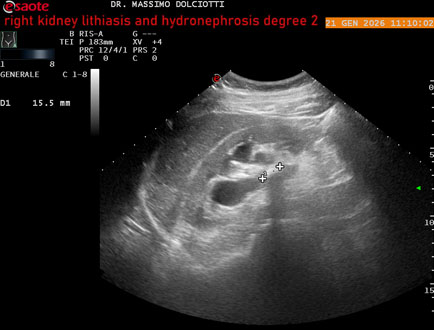

Data inserimento: 22/01/2026

Ecografia del: 21/01/2025

Strumento: Esaote MyLab Eight

Sonda: Convex Multifrequenza 1-8 MHz

Età Paziente: M 27 anni

Motivazione dell'esame: dolore al fianco destro da 3 mesi.

Commento all'esame: le immagini ed il video documentano il rene destro in sede, con ecostruttura disomogenea per evidenza, alla pelvi renale, di immagine iperecogena delle dimensioni di 16,2 mm, con cono d'ombra posteriore, da ricondurre a litiasi ed una formazione simile, di minore entità, al polo inferiore, delle dimensioni di 6,8 mm. Rene dx con diametro longitudinale di 122 mm (v.n. 90-120 mm) x 63 mm e parenchima renale dello spessore di 15 mm (v.n. > 13 mm). Rene dx con idronefrosi di 2° grado.

Conclusioni: litiasi e idronefrosi di 2° grado al rene destro (lithiasis and second-degree hydronephrosis of the right kidney).

In collaborazione: Dr.ssa Marica Manfredi - Ancona, Dr. Ilir Qose - Ancona

Presentazione: Dr. Massimo Dolciotti - Ancona

Elaborazione digitale: Andrea Dini - Ancona